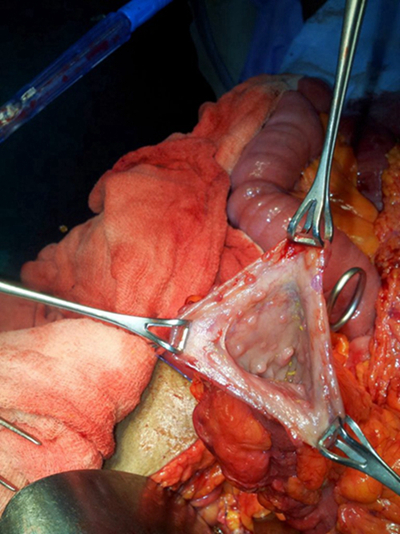

結腸癌症狀 (42)

結腸癌症狀 (43)

結腸癌症狀 (44)

結腸癌症狀 (45)

結腸癌症狀 (46)

結腸癌症狀 (47)

結腸癌症狀 (48)